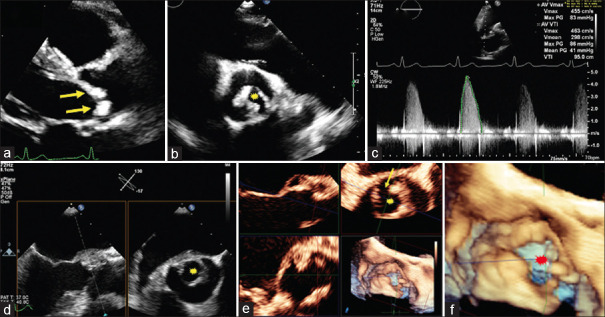

A unicuspid aortic valve (UAV) in adults is a very rare form of aortic valve (AV) malformation. UAV has two distinct subtypes, acommissural UAV and unicommissural, and can be differentiated by anatomical features, imaging modalities, and clinical presentation. With the development of significant AV lesion (s), surgical or transcatheter intervention will be required. The first part is a summarized review of UAV (anatomical features, clinical presentation, diagnostic modalities, and management). In the second part, we present a series of four patients diagnosed with UAV (3 unicommissural and 1 acommissural). The first case underwent balloon aortic valvuloplasty during childhood and surgical AV replacement later, with the progression to severe aortic stenosis (AS). The second case underwent a Ross procedure. The third and fourth cases were asymptomatic with moderate AS and mild-to-moderate AR and were kept on follow-up. In all the cases, transesophageal echocardiography confirmed the diagnosis of UAV with detailed morphological and functional assessment of AV.